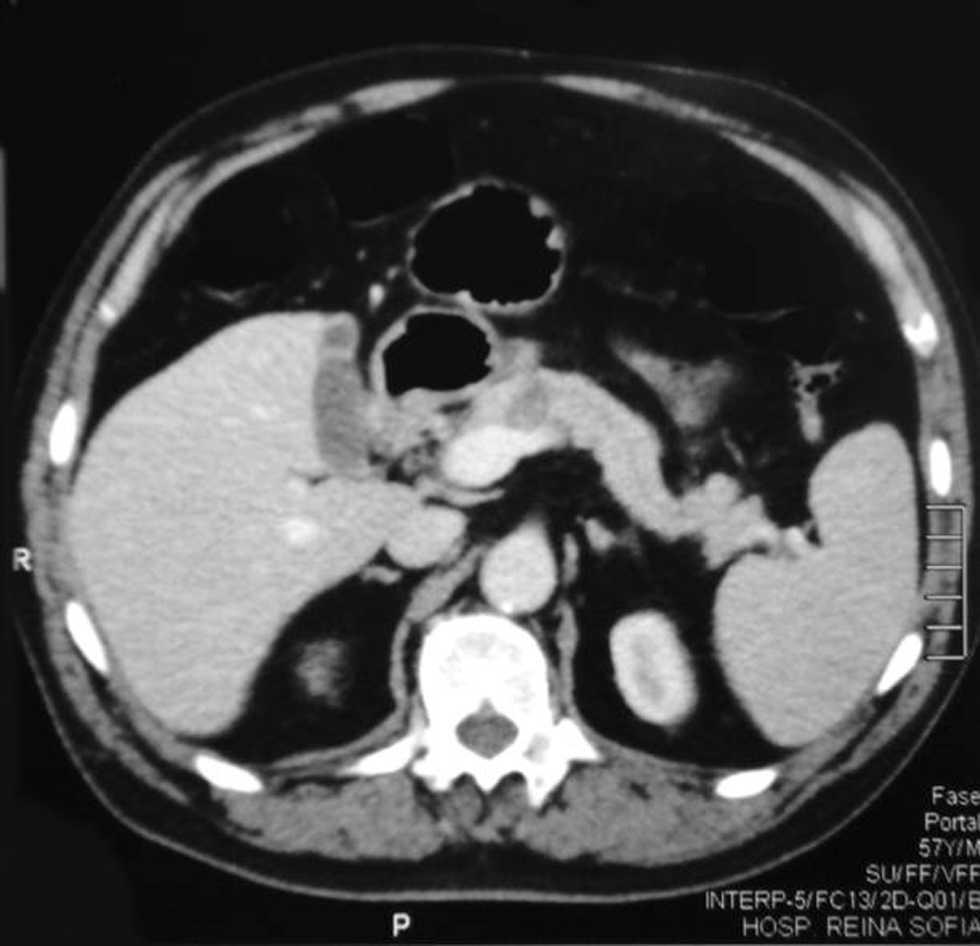

Se lo deriva a nuestro servicio para completar valoración y tratamiento; se realiza una tomografía computarizada abdominal con contraste intravenoso, que muestra una imagen hipodensa a nivel del cuerpo del páncreas, con arteria esplénica dilatada en su sector medio y dilatación del Wirsung (fig. 1).

Figura 1. Tomografía computarizada abdominal.